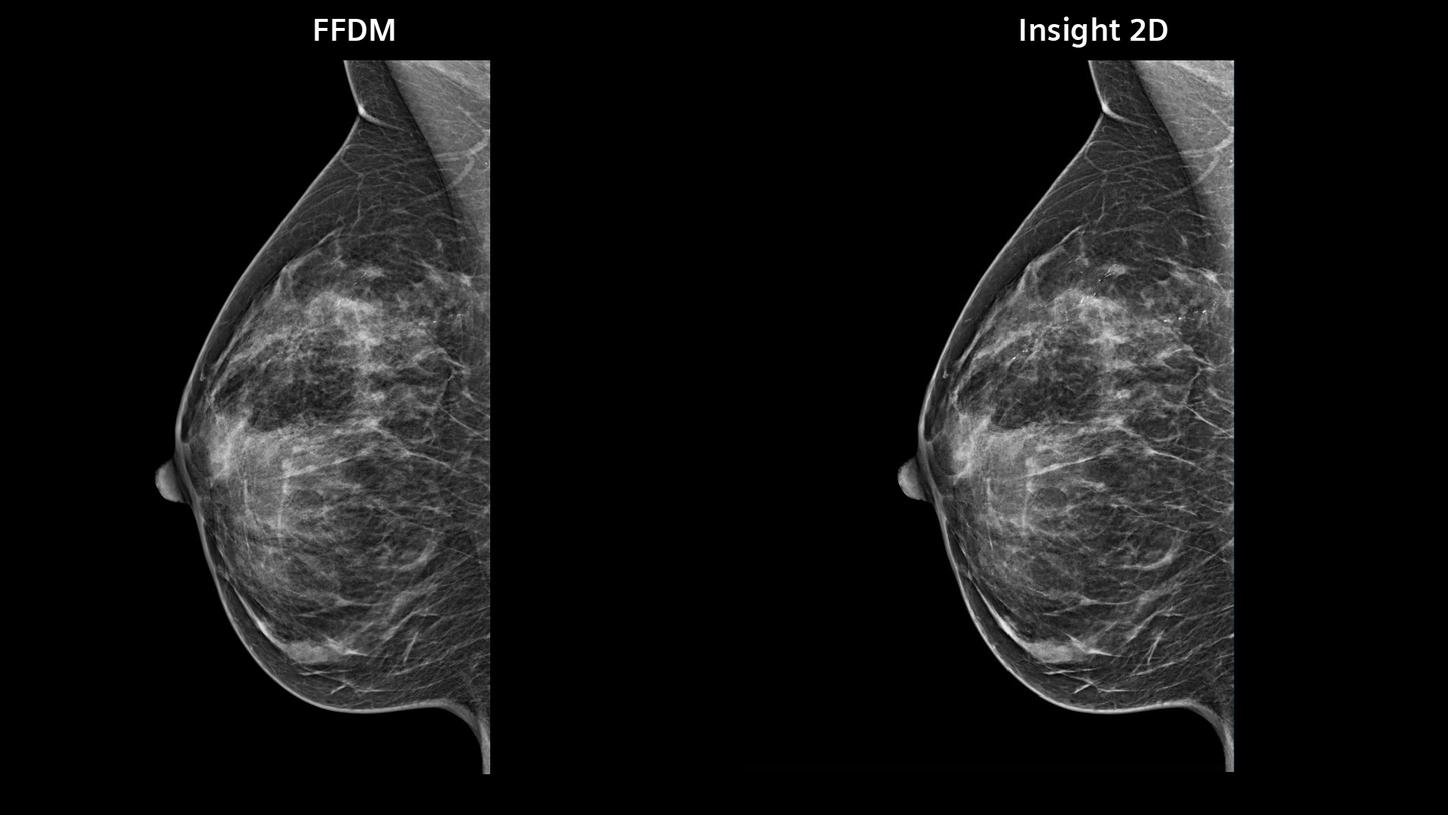

- Boost synthetic mammogram sharpness, thanks to AI-powered noise reduction

Image impression

5 different options for contrast and image sharpness for FFDM and synthesized 2D.